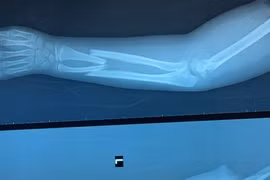

(GLO)- Sau 2 ngày cấp cứu tích cực, đến chiều 2-8, 2 người bệnh bị tai nạn giao thông nhập viện trong tình trạng nguy kịch đã được các y-bác sĩ Bệnh viện Đại học Y Dược-Hoàng Anh Gia Lai cứu sống.